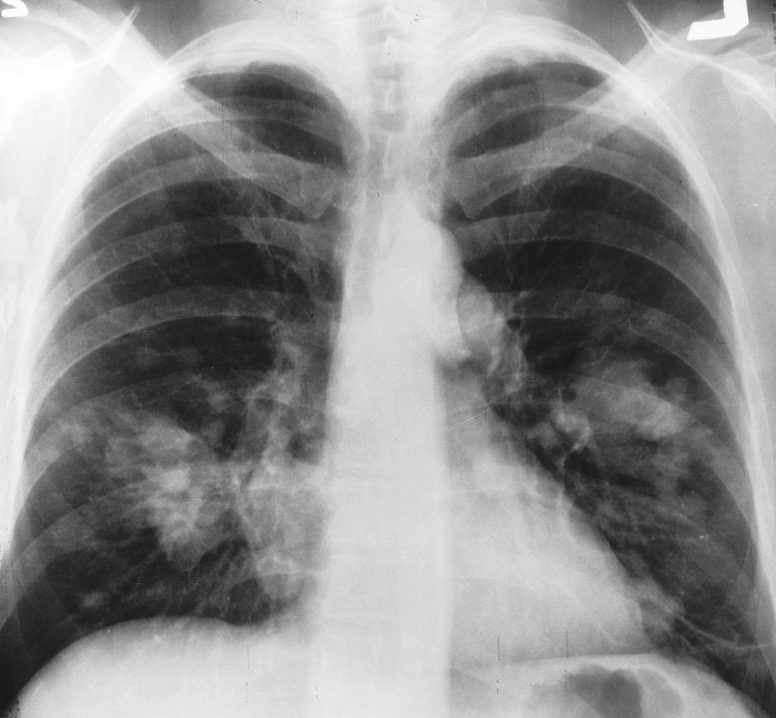

Il professore Lococo spiega che “Il nodulo polmonare è spesso l’espressione di una neoplasia allo stadio iniziale, pertanto più la diagnosi è precoce maggiori saranno le probabilità di guarigione. Cosa è cambiato oggi nella lotta al tumore del polmone? Al primo punto la prevenzione con la lotta al fumo, un più corretto stile di vita ma soprattutto i progressi nelle campagne di screening. Al secondo punto il ruolo delle linee guida con la stesura delle nuove linee guida nazionali a cura del PNR-Group. Al terzo punto la chirurgia mininvasiva, le moderne terapie biologiche e la più recente immunoterapia. Il tutto coordinato dai Gruppi Interdisciplinari del PDTA Oncologico”.